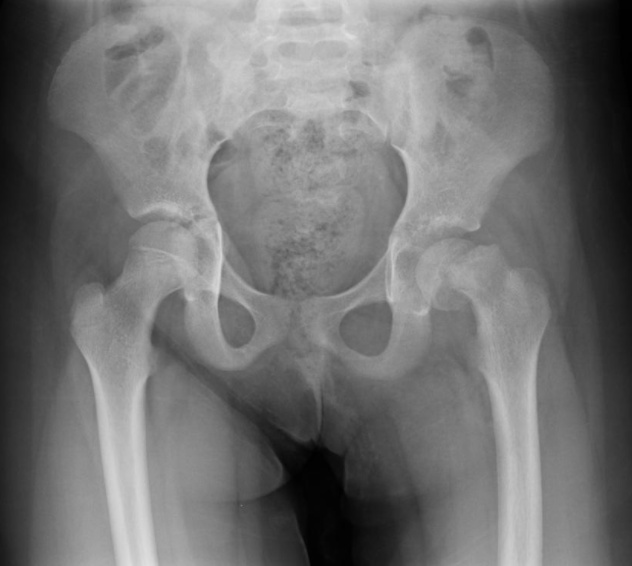

Radiographic findings include asymmetric hips visible on X-ray. Early findings include:

Medial joint space widening (earliest finding)

Small femoral head due to irregularity of the femoral head ossification center

Subchondral fracture.,

X-ray imaging including AP and frog leg lateral of both hips shows the epiphysis remaining within the acetabulum while the neck displaces anteriorly and externally rotates leaving the head posterior to the neck. An early radiographic finding is epiphysiolysis where the growth plate is widened or shows increased lucency.,